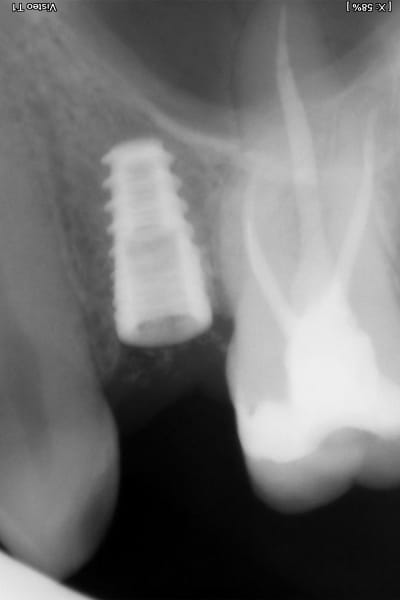

Zubní implantát je alternativním protetickým řešením, neboť chybějící zuby lze kromě klasického můstku klinicky vhodněji nahradit zubním implantátem, který splňuje všechny funkce původního zubu a navíc je jeho přirozenou a věrnou kopií, bez nutnosti zbrousit (degradovat) jiné okolní zuby (jako v případě můstku).